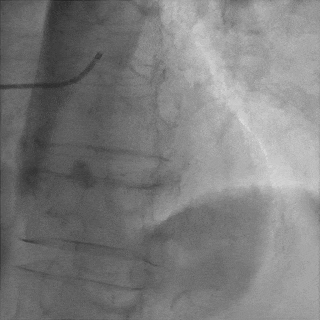

交换工作导丝至LAD远端

预扩球囊依次扩张LAD近中段病变处,造影可见远端血管显影,导丝位于真腔。

于LAD近中段植入Tivoli 2.75*33mm支架一枚,高压球囊后扩张后,血流TIMI3级